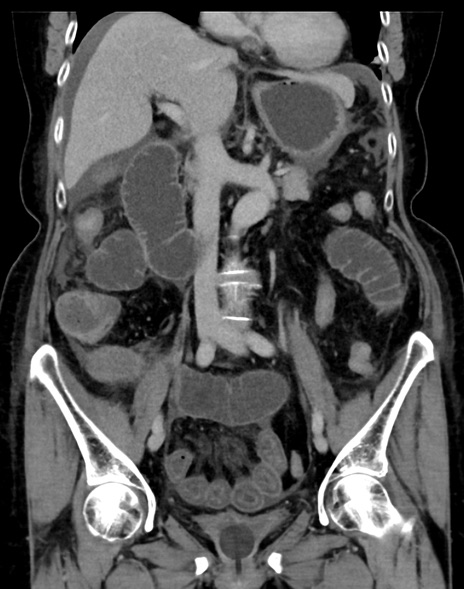

症例13 CT(冠状断像)1日半後

(横断像)1日半後